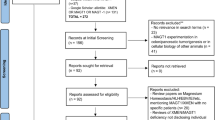

A total of 36 unique male patients have been reported [2,3,4,5,6,7,8, 10,11,12, 14, 15]. Females with heterozygous MAGT1 mutations are healthy carriers with a pattern of X chromosome inactivation (XCI) skewed toward the normal allele in their hematopoietic cells [1, 11, 12]. The disease appears to have complete penetrance with variable expressivity. MAGT1 has 10 exons, located on chromosome Xq21.1, and predicted to have multiple in-frame translation initiation sites with the predominant form encoding a 335 amino acid (AA) protein (UniProtKB-Q9H0U3). Most deleterious MAGT1 variants abolish protein expression (Table 1) [4].